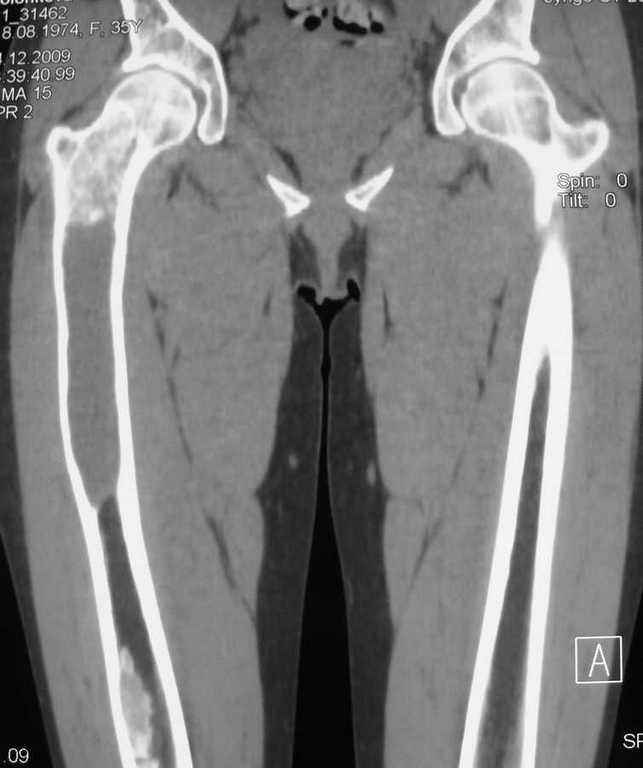

Re: Фиброзная дисплазия-продолжение